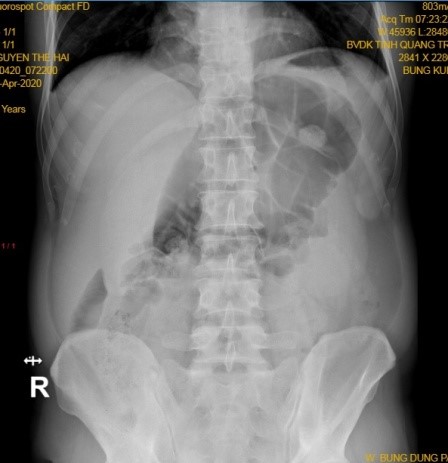

Vị trí của ruột thừa trong ổ bụng rất thay đổi cả trong mối liên hệ với manh tràng lẫn vị trí rất thay đổi của manh tràng trong ổ bụng khiến cho chẩn đoán viêm ruột thừa cấp trong các trường hợp này rất dễ nhầm lẫn với rất nhiều bệnh lý khác [3].

vị trí ruột thừa trong ổ bụng

Hình 4. Vị trí của ruột thừa trong ổ bụng

* Nguồn: theo Nguồn Schwartz(2007) [4]

Đau trong VRTC cũng rất điển hình, nó thường bao gồm 2 giai đoạn: ban đầu khi bị tắc nghẽn lòng ruột thừa căng lên kích thích các sợi thần kinh hướng tâm đi vào tủy sống T8-T10 gây triệu chứng đau nhẹ và mơ hồ ở thượng vị hoặc quanh rốn. Tuy nhiên kiểu đau này thường chỉ tồn tại khoảng 4-6 giờ cho đến khi quá trình viêm nhiễm kích thích phúc mạc lân cận ruột thừa gây đau khu trú [1],[4] và phản ứng (thường ở hố chậu phải- nơi ruột thừa cư trú). Trong trường hợp của chúng tôi ruột thừa nằm ở vị trí bất thường (giữa ổ bụng, đầu cắm xuống tiểu khung)  nên vị trí đau  cũng ở giữa ổ bụng. Ngoài ra nó được đại tràng xích ma và các quai ruột non che phủ nên triệu chứng đau khi khám bụng bị lu mờ và quả thực khám hố chậu phải bệnh nhân hoàn toàn không đau. Hơn thế nữa, do ruột thừa viêm nằm sau các quai ruột kích thích gây liệt ruột làm cho bụng càng ngày chướng hơn, giới hạn khả năng tiếp cận ruột thừa của siêu âm kết hợp với triệu chứng bí trung đại tiện và hình ảnh X quang bụng đứng có quai ruột chướng hơi lớn kiến các bác sỹ nội khoa nghi ngờ bệnh nhân bị tắc ruột và mời hội chẩn